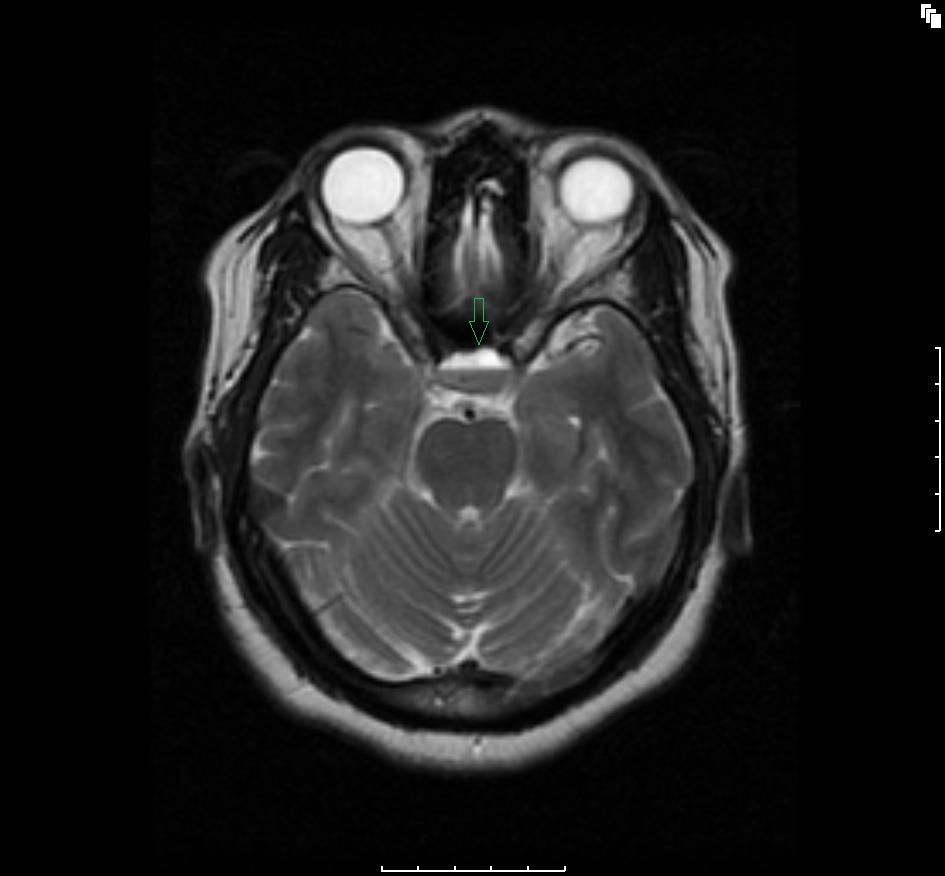

Figure A3: Axial flair T2-weighted 3 planar image showing a hypointense bottom layer and a hyperintense upper layer (green arrow) consistent with hemorrhagic pituitary macroadenoma.

The initial brain scans were obtained 6 months after her initial diagnosis (3 months into her pregnancy) and revealed a hemorrhagic pituitary macroadenoma (Figures A1-4). The patient recollects that a week before the scan, she suffered an episode of severe headache with visual disturbance of the right eye. She did not seek medical attention at the time but did keep an appointment for the brain imaging the following week. At the time of the imaging, she reported that her symptoms had fully resolved.